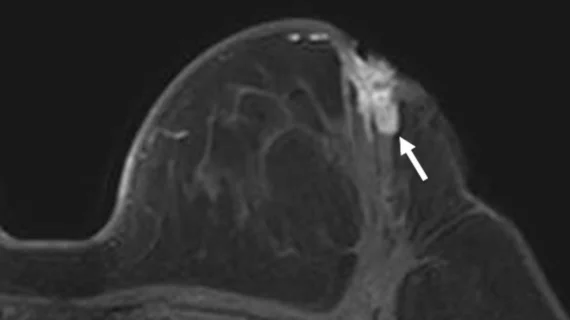

Physicians utilize medical imaging to see inside the body to diagnose and treat patients. This includes computed tomography (CT), magnetic resonance imaging (MRI), X-ray, ultrasound, fluoroscopy, angiography, and the nuclear imaging modalities of PET and SPECT.